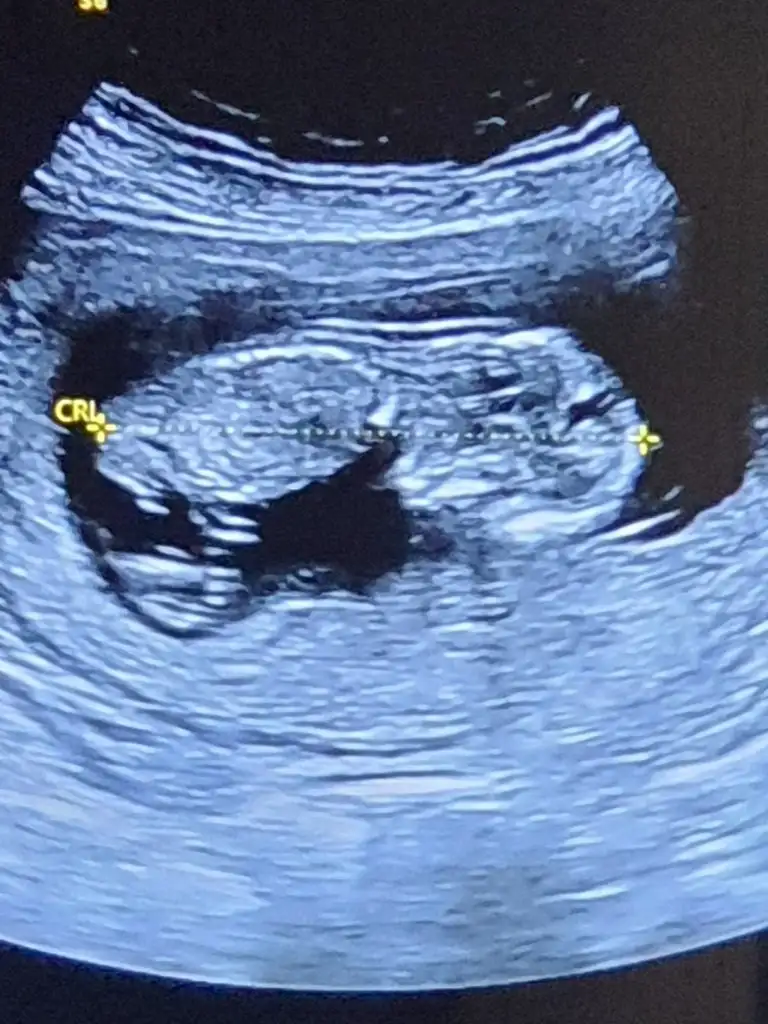

merhabalar banada yorum yapabilirmisiniz foto 12+4 tü şuan 15. haftadayım 2 oğlum var bu 3 cü olacak inşallah cinsiyetini çok merak ediyorum rabbim ilk önce sağlık versin

Kız gibi emin olamadım başka USG varsa paylaşın 11 12 13 haftalar olmalı